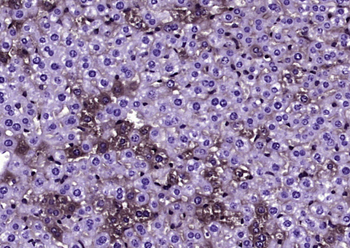

IHC staining of FFPE human brain with Ubiquitin antibody (clone PBQN-1). Required HIER: boil tissue sections in pH9 10mM Tris with 1mM EDTA for 10-20 min followed by cooling at RT for 20 min.

Western blot testing of human Raji cell lysate with Ubiquitin antibody (clone PBQN-1). Expected molecular weight ~9 kDa.